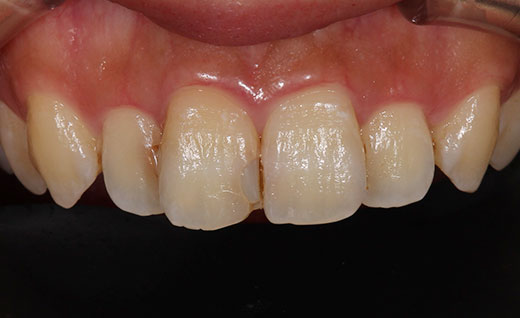

施術前

歯のホワイトニングを行われ白くなったのですが、以前に神経を抜いた前歯の色がすこし目立つようになってしまったので、今回オールセラミックで色を合わせさらにその横の歯の虫歯の治療も同時に行いました。

術後です。ホワイトニングをしたので術前に比べ歯は白く明るくなりました。また前歯の虫歯の治療もできるだけ目立たないように心がけ治療を行っております。術前では黒ずみや虫歯後がくっきり見えるのに対して術後ではほとんどわからず自然な見た目となります。